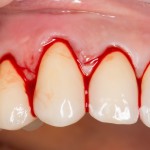

Всё начинается с анестезии и разреза десны. Разрез весьма специфический — по переднему краю межзубных сосочков. Это необходимо для того, чтобы эти самые межзубные сосочки сохранить:

Обычно на лекциях и семинарах показывают широко отслоенную десну, в пределах нескольких зубов. На самом деле, чем меньше разрез — тем лучше: ниже травматичность и обсемененность операционного поля микробами. Конечно, размер разреза должен быть не в ущерб нормальному обзору области вмешательства. Другими словами, разрез — это всегда компромисс. Между нормальным обзором и травматичностью.